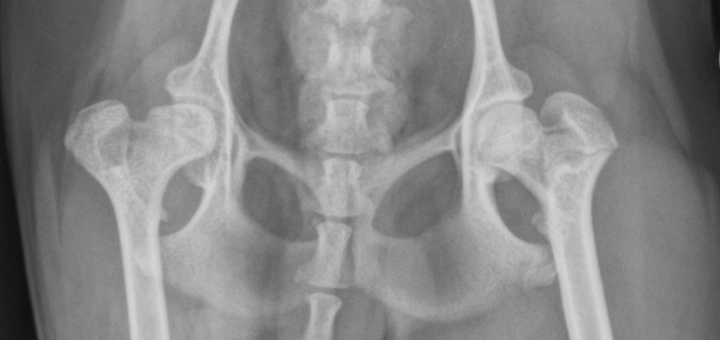

calve legg perthes signalment

immature toy/small dogs

unilateral

increased joint space, irregular femoral head

calve legg perthes